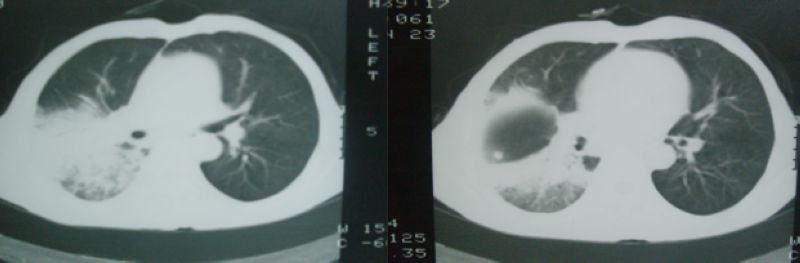

以下是引用随光逐影在2008-4-16 18:45:00的发言:[br]考虑为:肺部感染性病变;建议:抗炎治疗一周后复查。